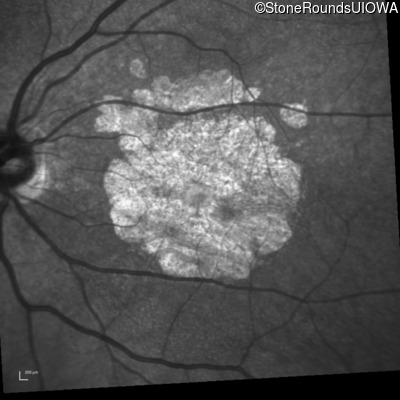

Blue Autofluorescence - Right - 10/300

Exemplar